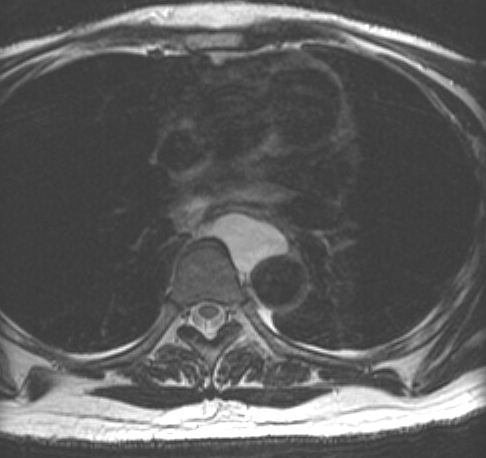

Gallery Congenital Bronch Cyst 2 MR

Bronch Cyst 2 MR